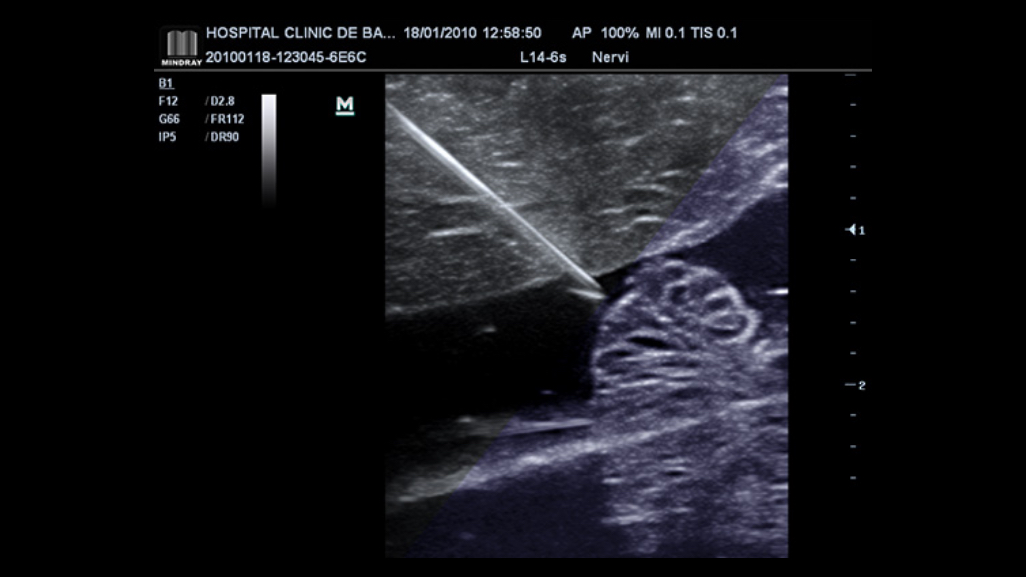

With its ergonomic mobile trolley same with performance and features comparable to that of conventional cart-based systems, the M7 Premium provides you mobility with power and improves your productivity. To sum it up, the M7 Premium delivers you the power and productivity of a full-sized system in a hand-carried size.

iScanHelper

Dedicated inbuilt tutorial software.

┬Ę Anatomical diagram illustrations including schematic and ultrasound picture

┬Ę Standard ultrasonogram comparison with real-time scanning

┬Ę Scanning reference picture demonstrating appropriate patient position and probe placement

┬Ę Tips on scanning skills and diagnostic information